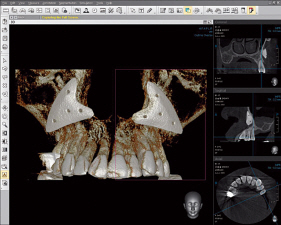

La radiología dental 3D ofrece al odontólogo informaciones muy detalladas para un diagnóstico más preciso y una mayor precisión en el tratamiento. La radiografía 3D le ofrece una visión más completa de la anatomía facial - prácticamente desde cualquier ángulo y perspectiva. Algo imposible de ver con imágenes 2D.

La radiología dental 3D es rápida y sencilla: en tan sólo segundos de escaneado le ofrece un estado completo de la zona bucal, maxilar y dental del paciente. Estas informaciones precisas y extensas pueden ayudarle a asesorar aun mejor a sus pacientes.

Visualiza la zona bucal, maxilar y dental desde una gran variedad de perspectivas

Puede ampliar cada área e incluso girarla

Nada permanece oculto: con la radiología dental obtendrá una imagen completa de la estructura oral, incluidos los huesos maxilares, estructuras blandas y nervios - todo ello con un único escaneado